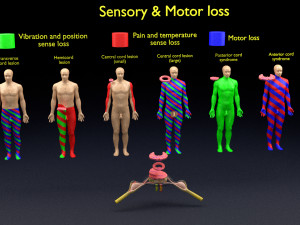

spinal fixation system - titanium bracket. human spine, spinal cord, sacrum and fixation system medically accurate high quality 3d model.

spine fixation spinal cord screw surgery system anatomy backbone bone brace bracer bracket column disc paralyze titanium treatment vertebra이 아이템에 대한 코멘트 없음.